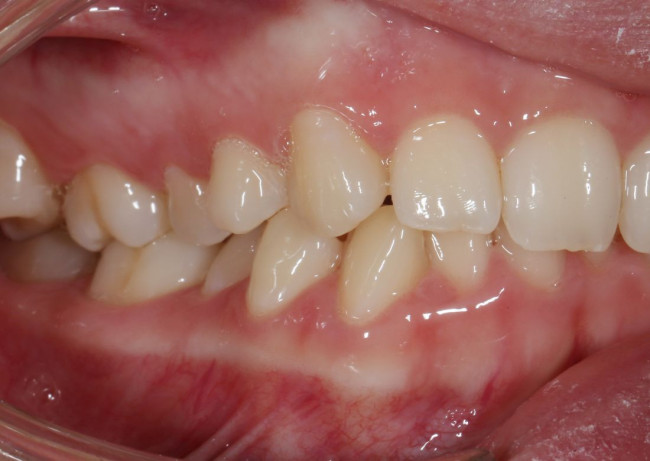

Колоссальный опыт стоматологов — визитная карточка клиники «Виртуоз» в Воронеже. Специально для вас мы создали страничку,

на которой разместили портфолио с работами наших врачей.

Мы регулярно добавляем фото до и после лечения, чтобы вы могли посмотреть финальный результат работы и оценить качество.

За каждой счастливой улыбкой стоит живая история, в которой мы принимали непосредственное участие. Мы всегда вникаем

в ситуацию наших пациентов и переживаем её вместе с ними.